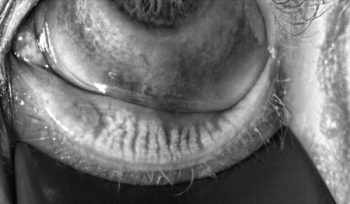

Comprehensive ocular examinations can provide an OD with an inside look into a patient's health. Mile Brujic, OD, and David Kading, OD, discuss the importance of using upper eyelid eversion during the exam to unleash significant information about a patient's ocular surface and systemic health.